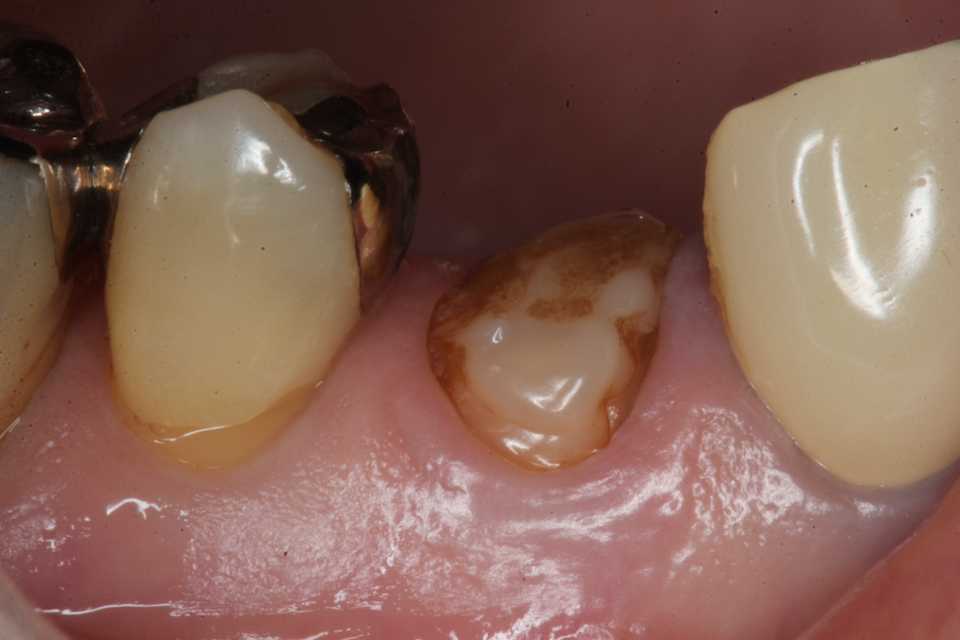

50代女性、左上5-7ブリッジ脱離、7番2次カリエス+Per(根尖性歯周炎)、強度の外傷性咬合この方、ひどい食いしばりで歯が壊れてしまう。噛み合わせの左下7番も歯冠が崩壊しつつある。7番はブリッジが脱離していて、内部は虫歯でドロドロ。Perつまり根管充填が緊密ではなく、歯根内部は細菌だらけで根の周りにはひどい炎症がある。まずはレントゲン写真から。7番の歯根の周りが炎症で黒くなっているのが分かると思う。ブリッジを全部外すと咬合が狂うので、とりあえず7番だけカットして内部を見てみた。根管充填材が見えるところまで軟化象牙質を除去して、3MIX+α-TCPを入れて根管内部を殺菌することにした。根管充填材の周りは黒くなっているのが見えると思うが、これは硫酸塩還元細菌の代謝産物の硫化鉄:FeSで、理想に反して根管充填材はゆるゆるの緊密充填ではないことを示している。このような状況は普通のことだ。歯根内部は細菌だらけということだが、ゆるゆるだから根管充填材を全部除去する必要もない。ゆるゆるの隙間から3MIX(抗菌剤)は浸透し根管は殺菌される。外傷力を弱めるために咬合調整を繰り返している。コア部分は隙間に細菌由来の黒色物質FeSがこびりつき、真っ黒。ポンティック下も細菌のコロニーでドロドロ歯質は残っているように見えるかもしれないが、ボンディング材が効く程度に軟化象牙質(虫歯)を除去すると、残根状態になる。つまり通常治療では抜歯しかないということだ。しかもPerでグラグラの動揺度2〜3、垂直性同様有りだ。とてもこのままではブリッジの支台には使えそうもない。ピンク色の根管充填材が見えると思うが、周りは真っ黒だ。その真っ黒になった隙間から細菌は侵入するし、3MIXも浸透する。こうではない緊密な根管充填治療は垂直加圧法でしか見られない。3MIX+α-TCPCR(ダイレクトボンディング)で覆う。これでないと微小漏洩が起こり失敗する。丸い形はラウンデッド・コアと呼び、この形が咬合力を内向きに集中させ歯根を守る。ポストは歯根の外側にこじるような応力を生じるので歯根を壊してしまいやすい。補綴物が必要な時はピンレッジで維持力を得る。これはCAD/CAMでは作れないだろう。これで2〜3週間様子をみる。外傷性咬合のコントロール(ナイトガードや行動療法)をしながら。つづく